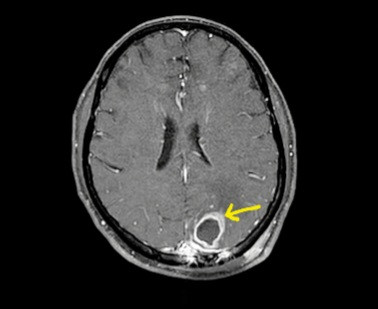

![]() |

| Bệnh nhân Whitmore bị ép xe não thuỳ chẩm đỉnh trái - Ảnh BVCC |

Mới đây, Trung tâm lại tiếp nhận một ca đặc biệt. Nam bệnh nhân L.D.D, 45 tuổi (Thái Bình), tiền sử đái tháo đường và làm nghề lái tàu trên biển, bệnh nhân được phát hiện có ổ áp xe trong não. Bệnh nhân vào viện Trung tâm Thần kinh cấy máu, mủ phát hiện vi khuẩn Whitmore, được chuyển sang điều trị tại Trung tâm Bệnh Nhiệt đới.

Sau hơn 20 ngày điều trị kháng sinh và hồi sức tích cực, bệnh nhân đã đỡ sốt, đỡ đau đầu, xét nghiệm ổn định. Tuy nhiên bệnh nhân cần được điều trị kháng sinh và theo dõi kéo dài ít nhất trong 6 tháng tiếp theo.